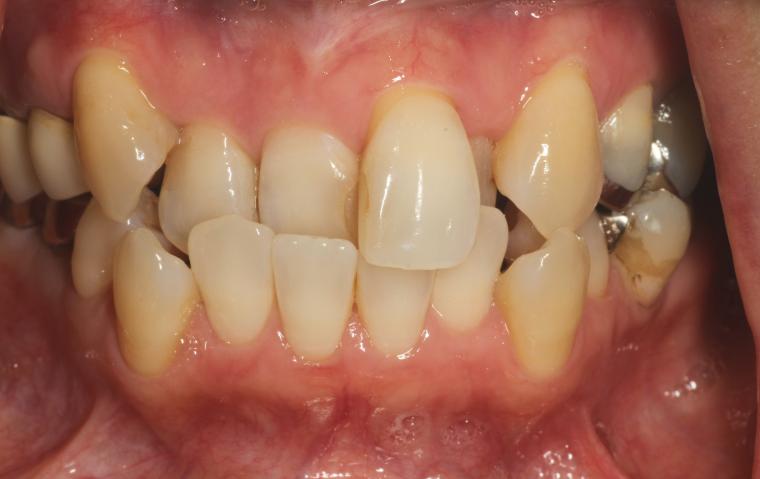

BEFORE

右下奥歯のお痛みが主訴でご来院の患者さんです。

右下第一大臼歯は、根っこの再治療をしました。

右下第二大臼歯は欠損していたため、マウスピース矯正で歯列を整えてから、インプラントを1本埋入しました。